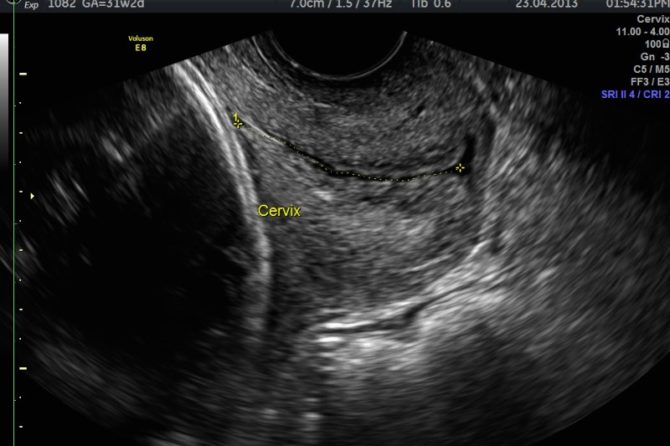

Cervical Length Assessment in Pregnancy

Preterm birth complicates about 8 to 10 percent of all births. A short cervix (< 25mm) or dilated cervix early in the second trimester of pregnancy appears to be a warning sign of impending premature birth among women who have previously given birth prematurely. Cervical length assessed by transvaginal sonography between 14 weeks and 24weeks, augmented by serial evaluations, predicts spontaneous preterm birth before 35 weeks’ gestation in high-risk women. The rate of preterm delivery at < 34 weeks’ gestation increases dramatically when the cervical length is ≤ 1.5 cm.

What exactly is the information obtained during cervical assessment?

- Length of the cervix

- Dilatation of the cervix

- Funneling of membranes into the cervical canal

A transvaginal scan is mandatory to accurately assess the features of the cervix as described above. The bladder is emptied prior to the scan.